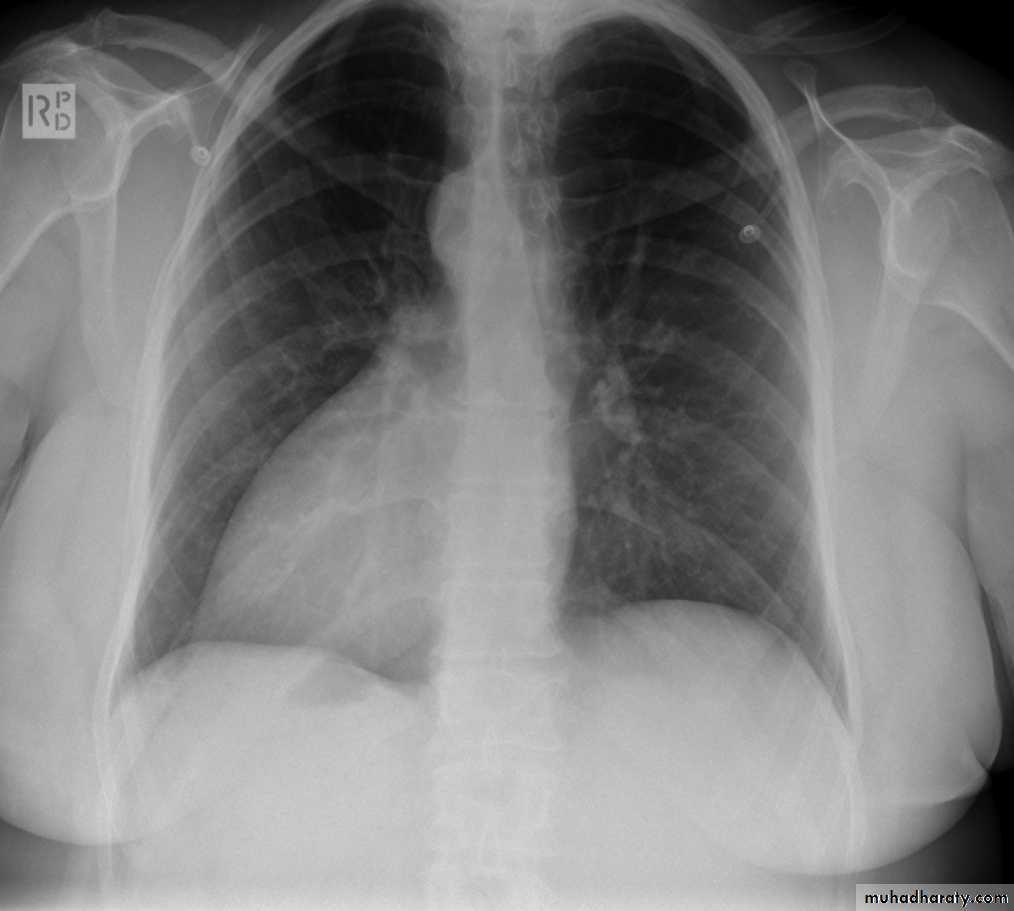

48.opasified hemi thorax

49.total collapse

Total collapse total consolidation

Total collapse